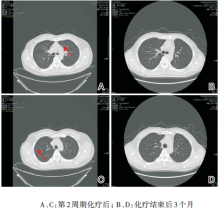

谢松喜:经科内讨论, 决定采用经皮肺穿刺活检+系统化疗+肺部手术+鼻咽部放疗的治疗方案。2013-08-01行经皮肺穿刺活检病理结果为肺浸润性腺癌。科室讨论此患者的诊断考虑为:鼻咽非角化型未分化癌伴双肺转移(cT3N1M1, Ⅳ C期), 左肺腺癌(cT1bN0M0, Ⅰ A期)。2013-08-16行第1周期TPF方案化疗(考虑本化疗方案同时对鼻咽癌及肺癌有效), 第2周期化疗后于2013-09-24复查胸部CT提示:与治疗前对比, 原发灶缩小, 转移灶减少、缩小(见图3)。治疗有效。予以继续完成共4周期TPF方案化疗。化疗结束后于2013-11-08行全胸腔镜下肺叶切除术+肺门纵隔淋巴结清扫术, 术后病理:(左下肺)肺浸润性腺癌, Ⅱ 级, 淋巴结可见癌转移(共1/9, 其中“ 段LN” 1/1)。术后恢复良好, 于2013-12-13开始行鼻咽+颈部调强放疗, 剂量66 Gy/30 F, 2014-01-23结束全程放疗。放疗后定期复查鼻咽MRI提示鼻咽肿瘤消失(见图4)。2014-07-08复查胸部CT示:左肺上叶前段结节较前增大, 考虑恶性可能性大。右肺两个小结节, 变化不大(见图5)。 此时, 我们需要明确:(1)诊断是否要改变?肺部小结节是良性或恶性?是肺多原发癌或鼻咽癌或肺癌转移?(2)左上肺新发增大的肺部结节如何处理?

图3 胸部CT提示肺转移灶减少、缩小